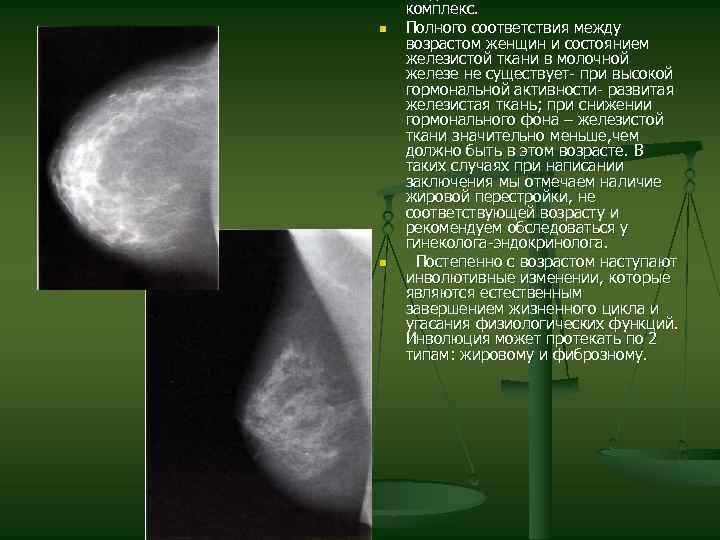

Что такое маммография: важность, процесс и результаты

Раздел: Необычные решения